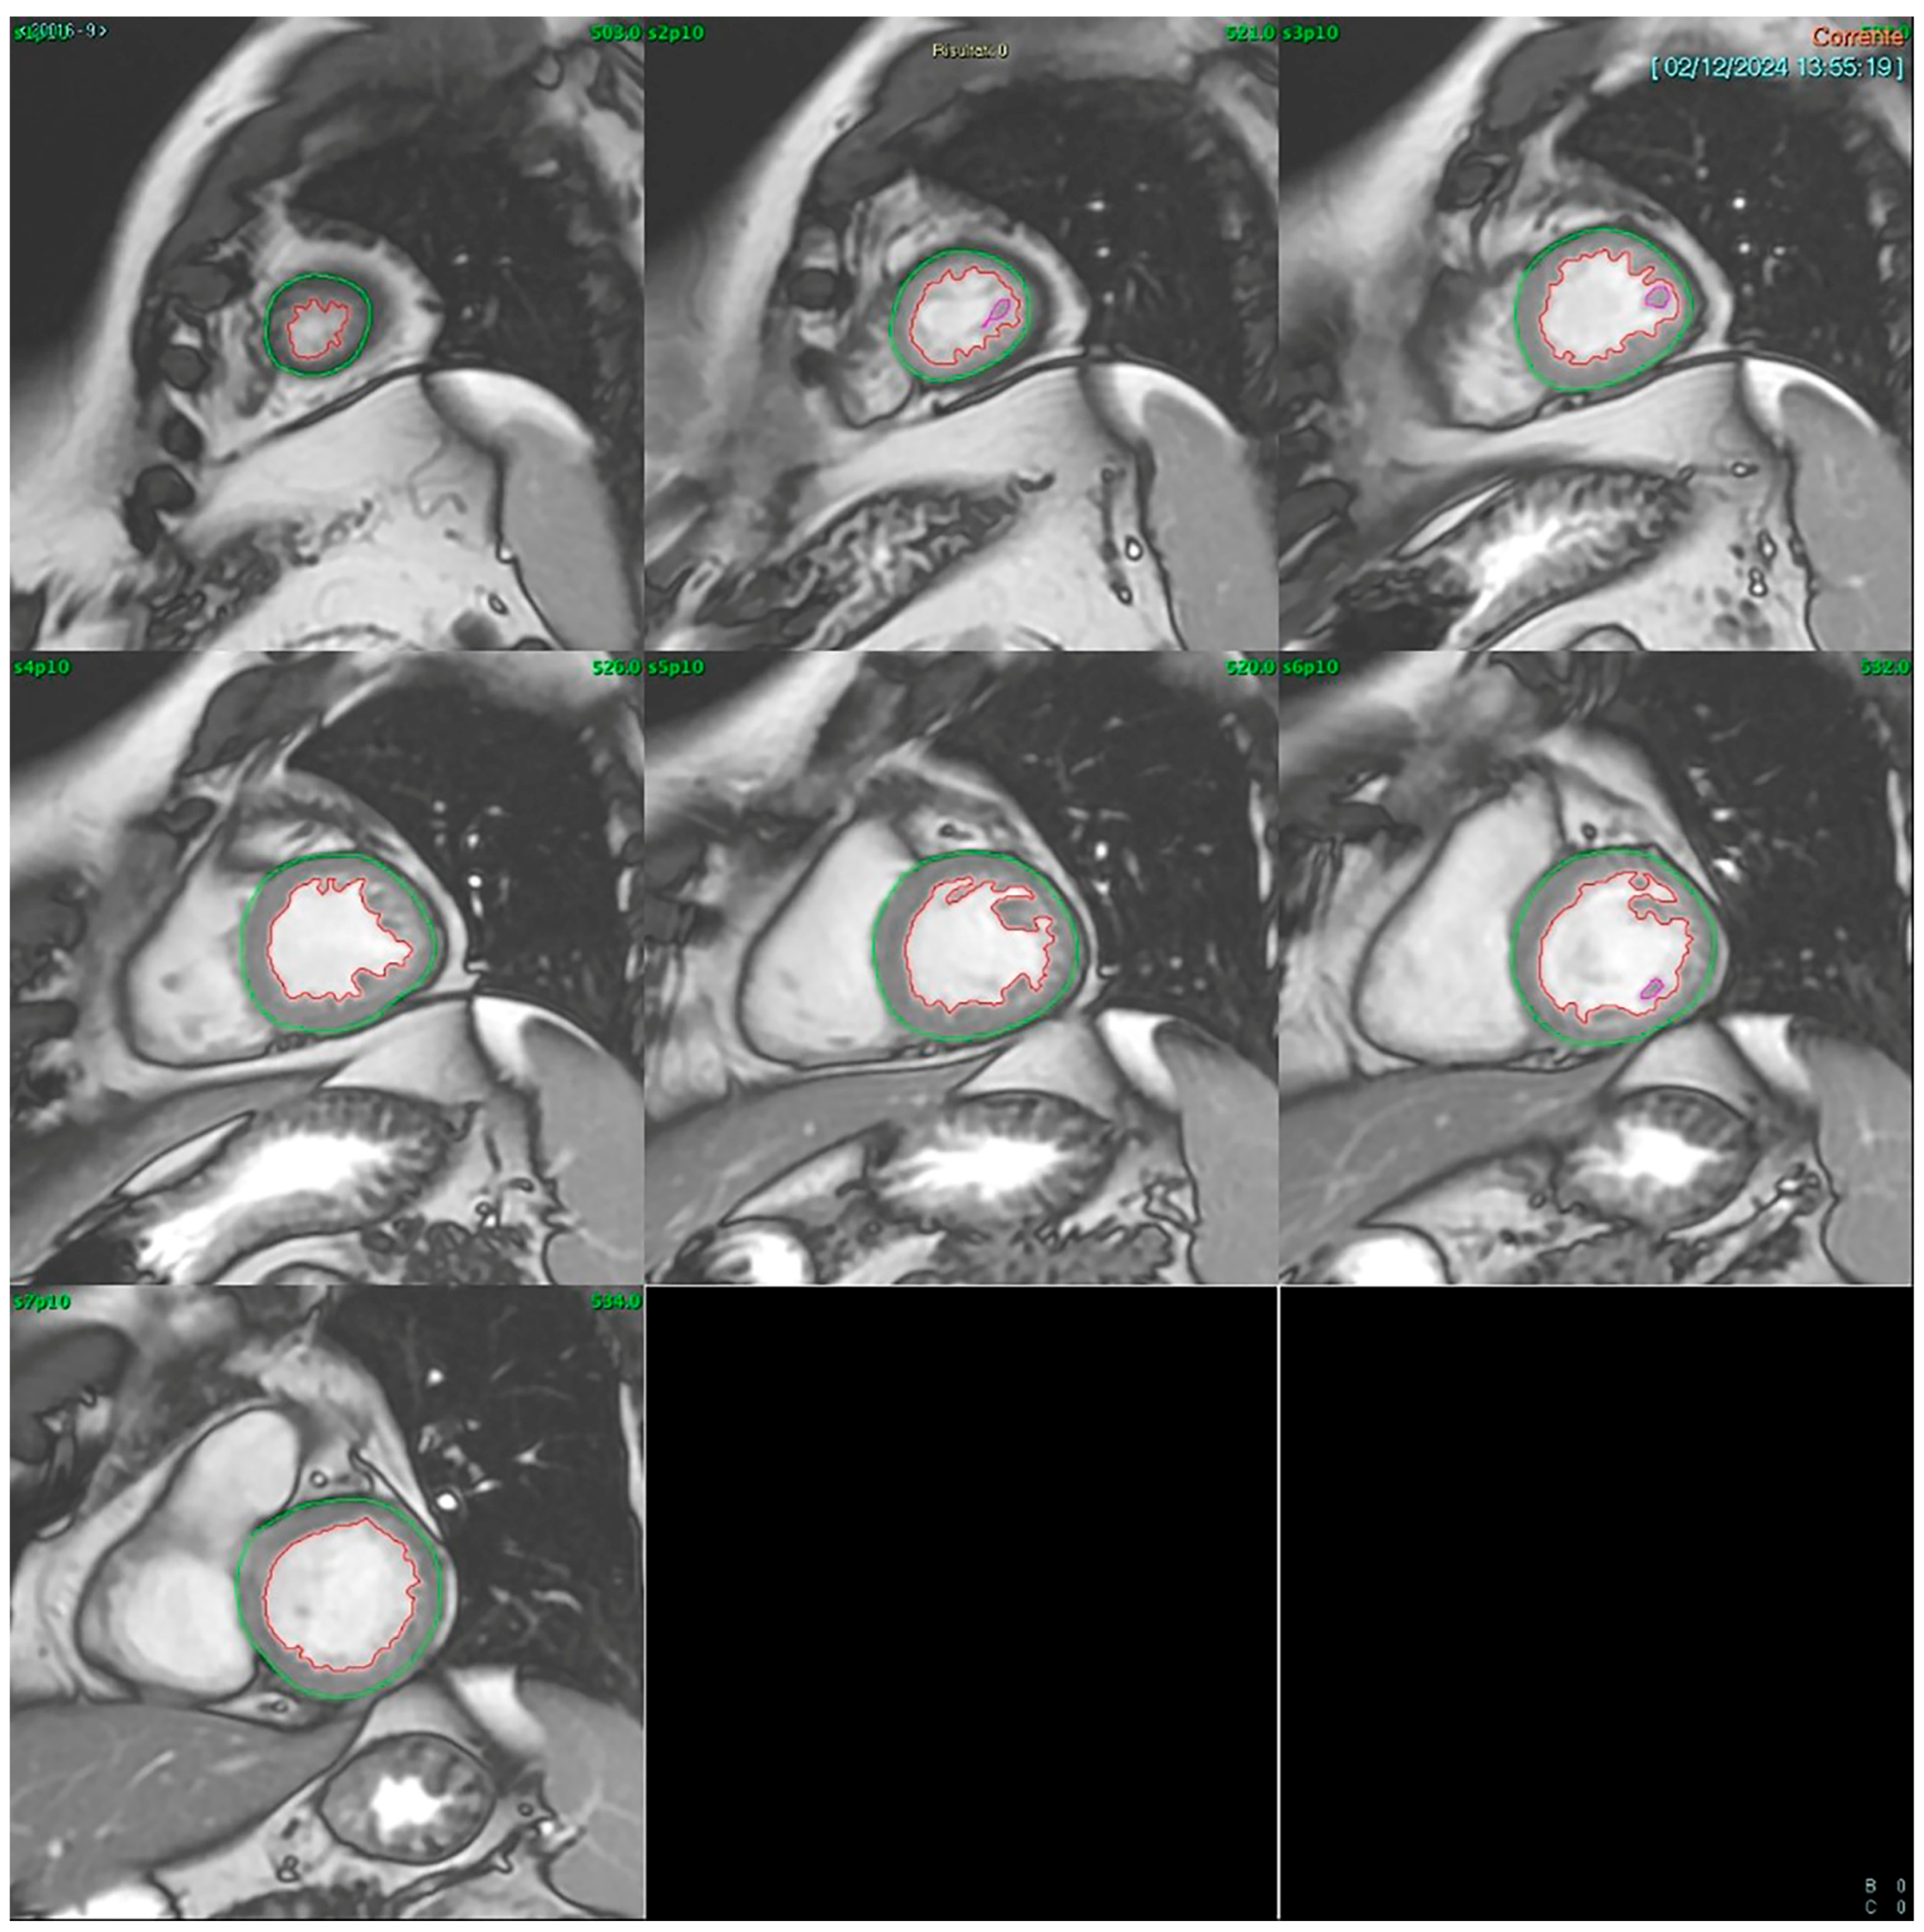

Cardiac MRI (CMR): CMR was conducted using a GE SIGNA™ 1.5T system (General Electric (Healthcare), Boston, MA, USA). Multishot fast spin-echo sequences were acquired along the short and long axes for morphological evaluation, while cine-MRI fast gradient echo sequences in respiratory apnea were used for dynamic assessment. Short-axis images included 8–9 contiguous slices with 10 mm thickness, covering the entire left ventricle and capturing at least 20 cardiac phases per slice. LVEF was calculated using the Simpson rule (method of disks) applied to a contiguous short-axis cine stack acquired via SSFP sequences. The left ventricular end-diastolic and end-systolic volumes were manually traced in each slice from base to apex (Figure 1). All analyses were performed offline by a single experienced CMR reader using blinded echocardiography results.

Figure 1. Automatic contouring of the left ventricle on an SSFP contiguous diastolic short-axis cine images stack from base to apex.